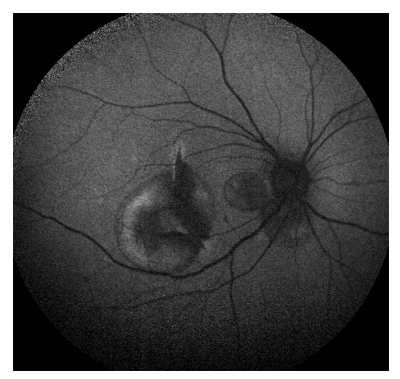

1 病例资料

患者,男, 16岁,体校学生,汉族,因“右眼眼前黑影遮挡,伴视力下降 2 周”为主诉入院。 2周前无明显诱因出现右眼眼前黑影遮挡,伴视力下降,不伴眼红、眼痛、畏光、流泪等症状。既往体健,生命征平稳,心肺腹未发现明显异常。眼部情况:右眼视力0.02, -3.00DS/ -1.25DC*171=0.25,左眼戴镜视力0.4, -1.75DS/ -1.50DC*9=1.0,双眼眼前节情况可,左眼眼底大致正常。右眼眼底及辅助检查(图1~6):黄斑区见一不连续弧形黄白色病灶,其周围见类圆形出血性神经上皮脱离(图1)。自发荧光显示黄斑区多个弧形呈低荧光病灶,黄斑去血性神经上皮脱离,部分因血自发荧光增强(图2)。行光学相干断层扫描血流成像(optical coherence tomography angiography,OCTA)检查,在视网膜无血管层可见弧形低密度区及网状CNV结构(图3),在脉络膜毛细血管层见经过黄斑中央脉络膜毛细血管弧形缺损区,暴露其下脉络膜中层血管(图4)。行荧光素钠造影(fluorescein angiography,FA)联合吲哚菁绿造影(indocyanine green angiography,ICGA)检查,ICGA见经过黄斑中心凹处一新月形弱荧光,视盘颞侧见多处小弧形弱荧光,均为脉络膜破裂部位。破裂病灶对应线扫光学相关断层扫描(optical coherence tomography,OCT)图RPE-Bruch膜复合体及脉络膜毛细血管断裂处,凹陷处见中高反射瘢痕信号,FA可见弧形染色并且中央有楔形荧光渗漏,考虑有脉络膜新生血管(choroidal neovascularization,CNV)形成可能(图5)。诊断:右眼多发性脉络膜破裂并CNV形成、黄斑视网膜下出血、双眼屈光不正。治疗上予玻璃体腔注射抗血管内皮生长因子(vascular endothelial growth factor,VEGF)治疗后1个月随访,视网膜下出血吸收,矫正视力提高到0.6(图6)。

20230131163615_3755.png

图1 黄斑区见一不连续弧形黄白色病灶,其周围见类圆形出血性神经上皮脱离

Figure 1 A discontinuous curved yellow-white lesion with quasi-circular hemorrhagic neuroepithelial detachment is seen around the macular area